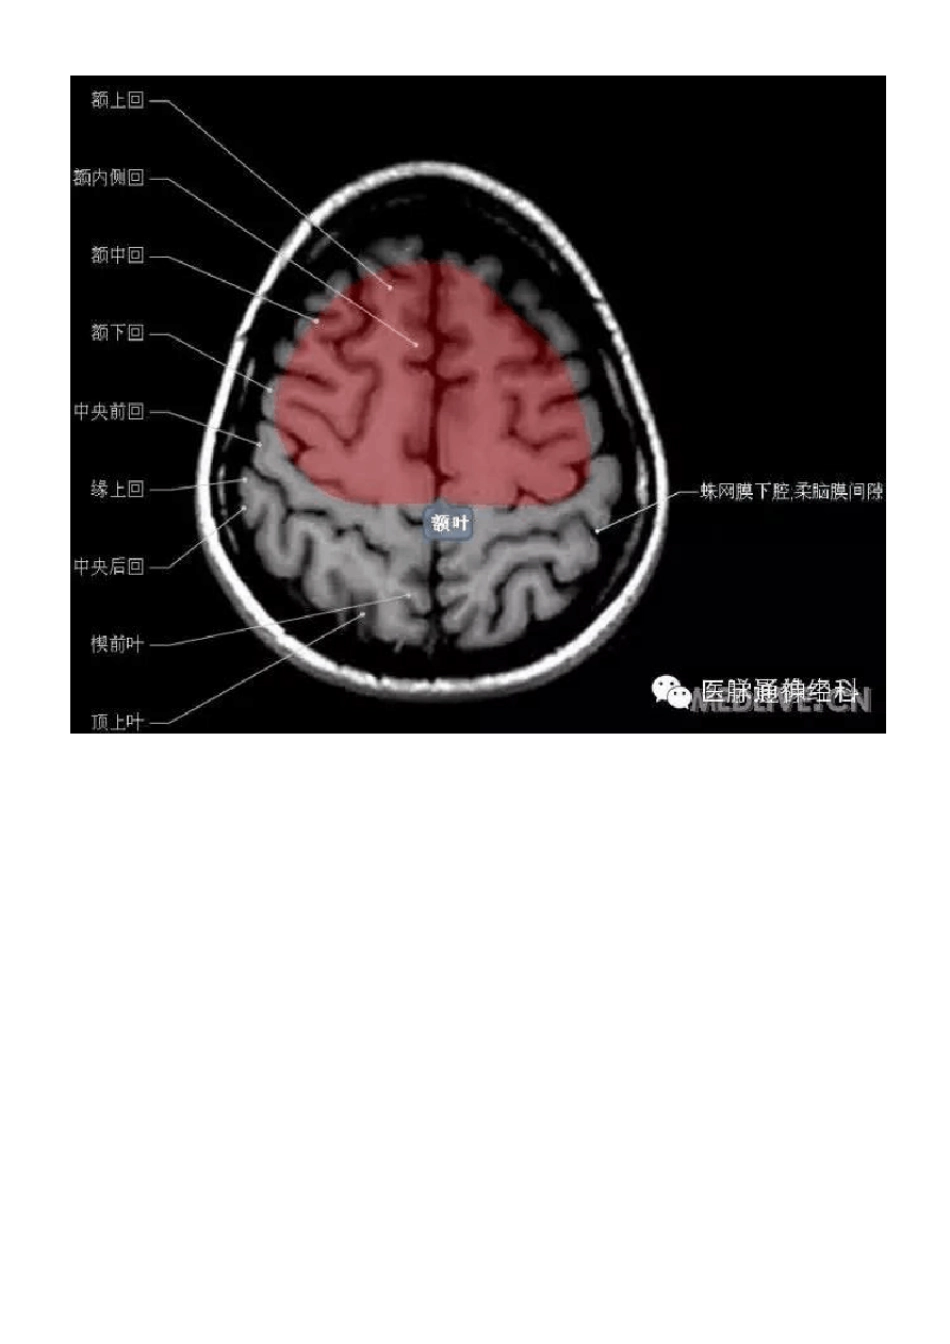

正常颅脑MRI 图示

正常颅脑磁共振图示